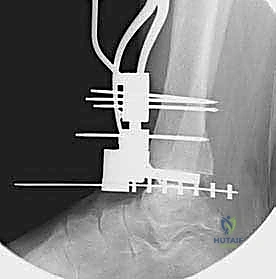

4. وضع أدلة القطع (Jig Placement and Alignment)

تعتمد دقة الجراحة على المحاذاة الصحيحة. يتم استخدام أجهزة توجيه متطورة (Jigs) تثبت على عظمة الساق باستخدام دبابيس معدنية. يتم التحقق من صحة الزوايا والمحاور باستخدام جهاز الأشعة السينية المباشر داخل غرفة العمليات (C-arm Fluoroscopy). يضمن الدكتور هطيف أن يكون القطع موازياً للأرض تماماً عند وقوف المريض.

5. القطع العظمي الظنبوبي (Tibial Bone Cut)

باستخدام منشار جراحي دقيق التذبذب، يتم إزالة شريحة رقيقة جداً (بضعة مليمترات) من السطح السفلي التالف لعظمة الظنبوب. يتم القطع بحذر شديد لتجنب إصابة الأوتار الخلفية أو الأوعية الدموية.

6. القطع العظمي الكاحلي (Talar Bone Cut)